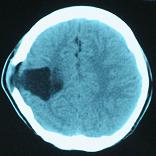

头颅CT和MRI可见颅骨缺损区下方软脑膜囊肿、脑软化灶或脑室穿通畸形(图2)。

图2:①和②CT及骨窗相显示右顶部颅骨缺损,其下方脑组织呈低密度改变;③-⑥MRI右顶局部颅骨缺如,脑组织轻度向外膨隆,右顶叶侧脑室体部旁局部脑组织缺如,代之以囊性长T1、长T2信号。